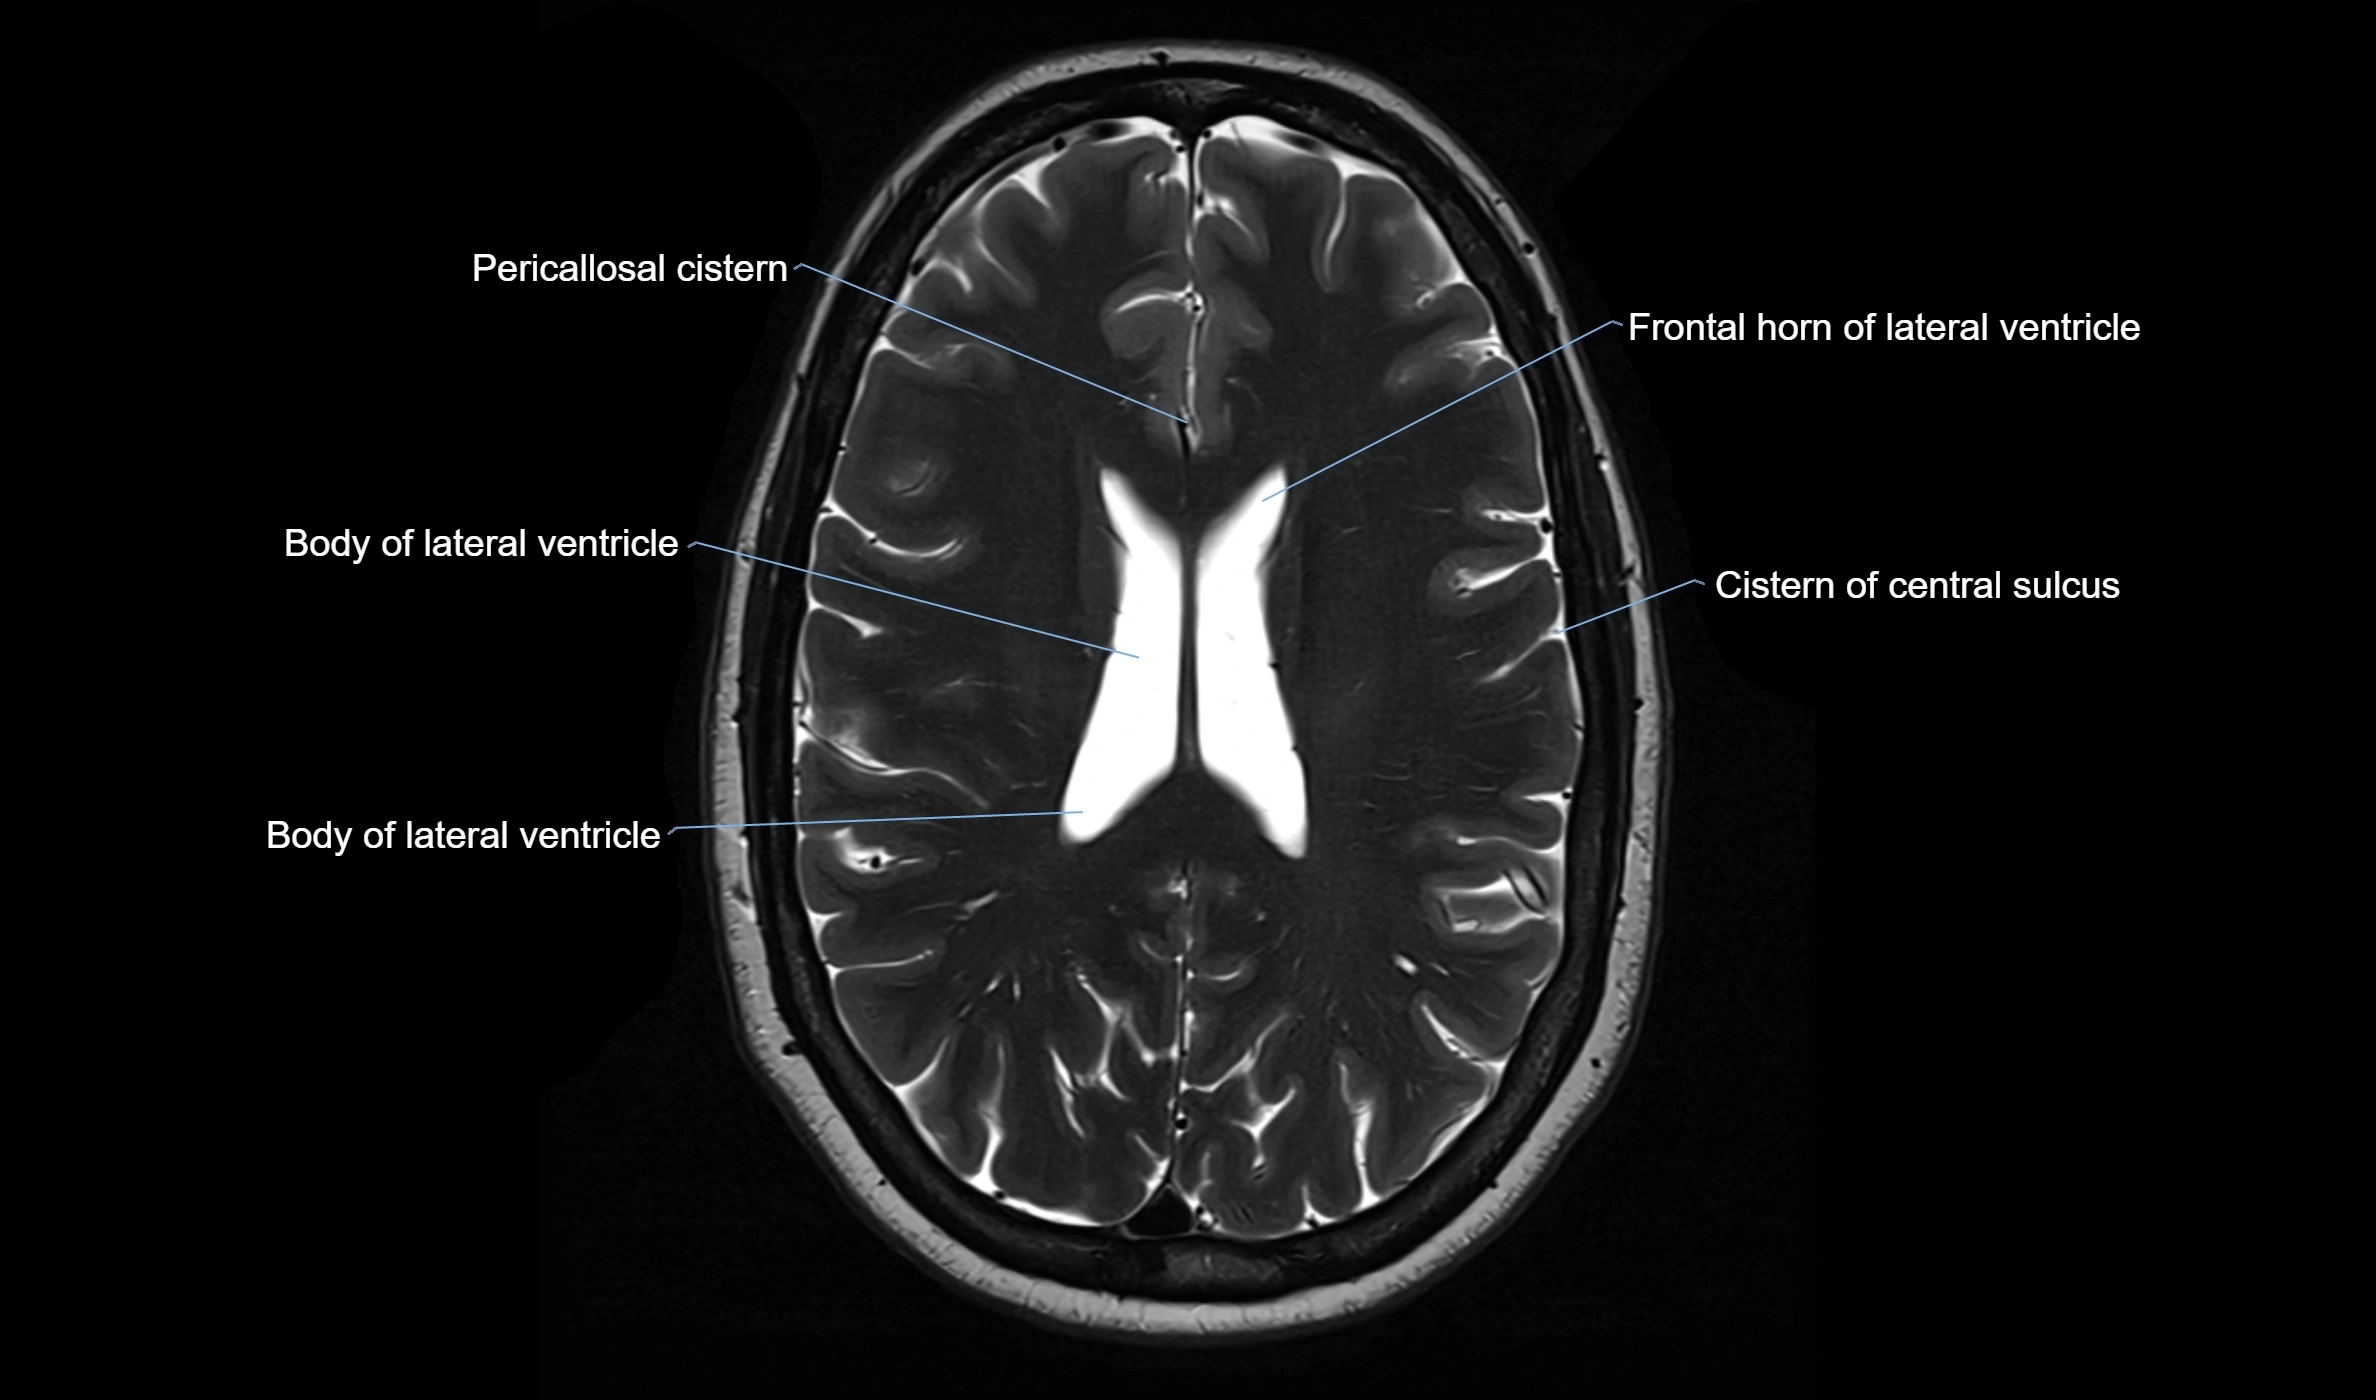

MRI images

image